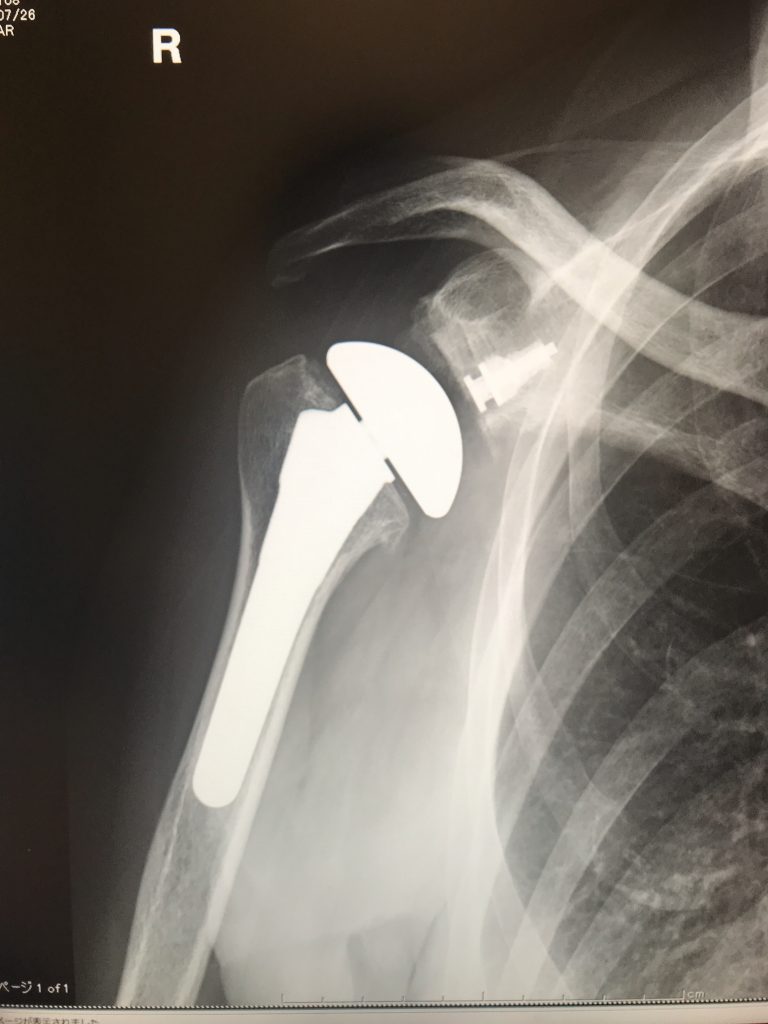

しばらく来なくなってしまっている患者さんは名前だけでは顔が思い出せなくても、画像とオペ記録を見ると、ぱぁっと顔が思い浮かびます。